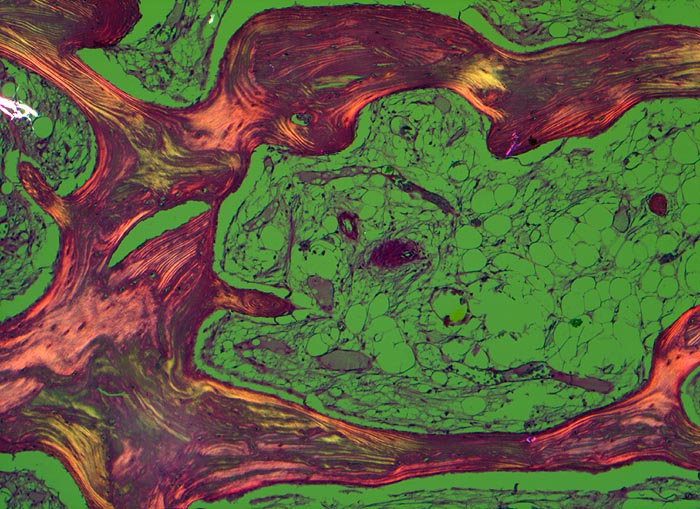

An den betroffenen Stellen ist sowohl der Knochenabbau als auch der Knochenanbau gesteigert. Die Osteoklasten sind auffallend gross und enthalten sehr viele Kerne (> 3518). Die aktivierten Osteoblasten produzieren verdickte und grob geflochtene Spongiosabälkchen. Der neugebildete Knochen ist strukturell und morphologisch abnorm und schlecht mineralisiert. Der Knochen wird dadurch weich und anfällig auf Frakturen oder Deformation unter Belastung (nach vorne gebogene Säbelscheidentibia). Das Knochenmark wird ersetzt durch fibrovaskuläres lockeres Stroma, welches an Granulationsgewebe erinnert. Mikroskopisch werden eine osteolytische Initialphase, eine Umbauphase mit verstärkter Knochenneubildung und eine sklerosierende Stabilisationsphase mit strukturellem Umbau und Spongiosierung der Kortikalis (verbreiterte spongiosaartige Kortikalis) unterschieden.

• Die Spongiosabälkchen sind auffallend verdickt, vermehrt und unregelmässig geformt.

• Prominente Zementlinien sind mosaikartig angeordnet.

• Riesenosteoklasten mit über 20 Kernen sind an der Knochenoberfläche erkennbar.

• Vermehrte kubische aktive Osteoblasten bauen Knochen an.

• Lockere Markfibrose.